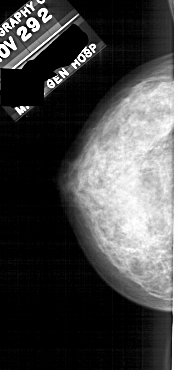

A_1808_1.RIGHT_MLO

RIGHT_MLO LINES 4996 PIXELS_PER_LINE 2431 BITS_PER_PIXEL 12 RESOLUTION 43.5 OVERLAY